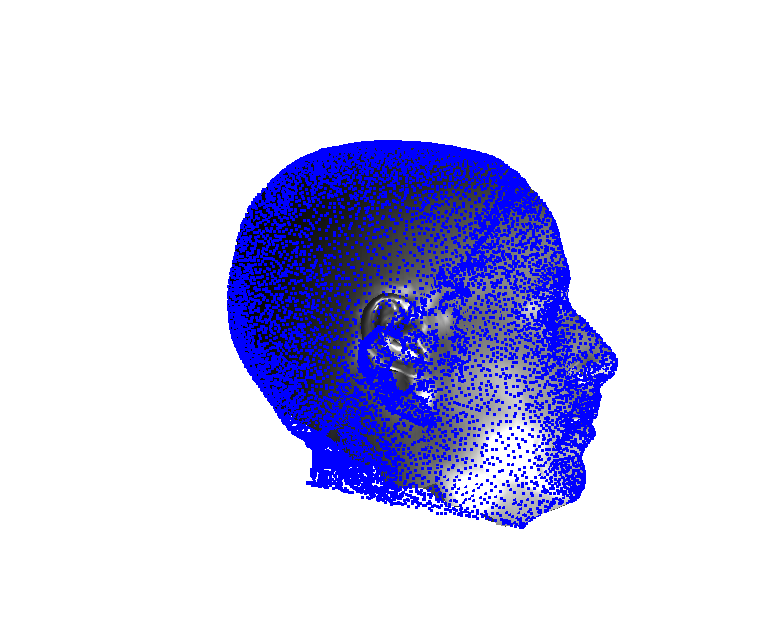

Toolsets to define normal appearance and therefore both assist with planning of surgery and define optimal outcomes from a range of surgical interventions are currently either crude or lacking. Therefore, the unit collected a large, high quality 3D image dataset of 1523 human heads. An example is given in Fig. 1 showing the 3D channel only on the left, and the 3D data with texture pasted on on the right. The data was collected over well-conserved demographics, and an age range of 1 to 89 years, see Fig. 2. The dataset was collected with the aim of developing a normal equivalent of the human cranium and face in order develop the tools to enhance patient experience following surgery. We plan to make the dataset publicly available in the near future.

Our system can accept 3D images in arbitrary pose and employs an automatic landmarking scheme to normalise the pose of the 3D head before any further processing. Two examples of typically varying initial pose taken from the headspace datset are shown in Fig. 4.

Fig. 9 shows examples of the fitted model (trained on FRGC data) on the first four subjects in our Headspace training set. Note that the mean of the landmarks in the sparse model is centred on the orgin, and so the scan data is moved towards that and becomes frontal in pose. We note that other researchers [28] have used 3D landmark localisation to find the head, but often this only includes landmarks that are relatively easy to localise, namely inner eye corners and nose. Localising more landmarks over a wider facial area has a number of advantage in terms of cropping, pose normalisation and global 3D template warping, all of which are described later.

7 Extension to 3D full head modelling

Pose is normalised using the ECN method, and relies on the symmetry plane, ellipse centre and nasion position, as shown in Fig. 25. We then find a set of pseudo-landmarks on the cranial surface by 3D ray projection over a predefined set of angles, as shown in Fig. 26. The same processes are applied to a template mesh of the human head, so that it has the same set of both face and cranium landmarks.

The template mesh is then warped in a global affine sense, as shown in Fig. 27 to minimise the least-squares error between the two sets of landmarks, when the head scan is fixed in its canonical poose. After this initial stage, landmarks and pseudo-landmarks are used in the same way as any other mesh vertex, as they are potentially noisy, as seen in earlier results analysis. This contrasts with Amberg et al’s [11] approach where the influence of landmarks is gradually faded out.

Following this, OSNR ICP iterates over a set of decreasing mesh stiffnesses (typically 10), until the registration between the template and the scan is below some error or a maximum number of iterations is reached. Figure 28 shows a selection of template warp results. The template appears to be accurately warped onto the scan, at least in the normal direction of the surfaces, it is not possible to see error tangential to the surface. Furthermore, we have noted errors on some scans on the ears. To improve these we need a method of automatically landmarking the ears, which is an area for further work.